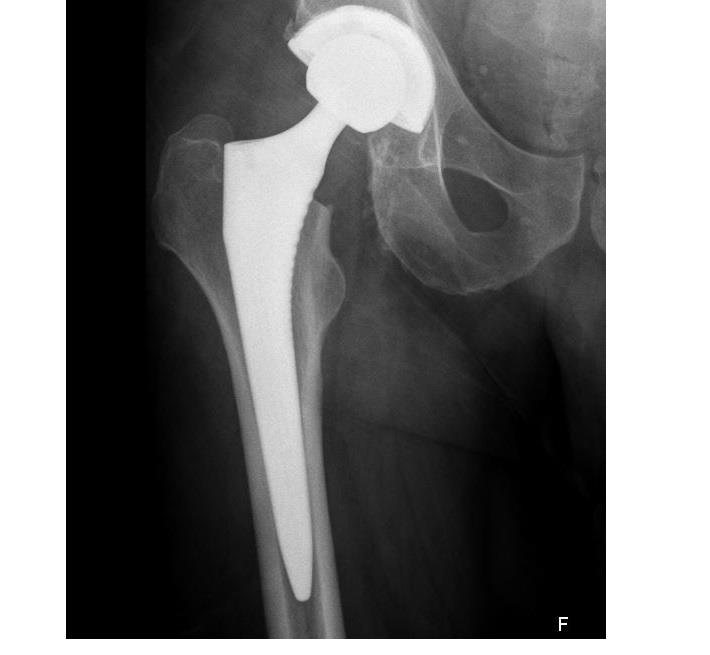

בניתוחי החלפת מפרק הירך מוחלפים שני צדי המפרק במשתלים מלאכותיים: בצד עצם האגן מושם משתל בצורה כיפה קעורה ("המכתש") ובצד עצם הירך משתל קמור ("תפוח").התנועה הסיבובית של המפרק נוצרת בין המכתש לתפוח.באזור המפרק בין המכתש לתפוח ישנן אפשרויות לשימוש בחומרים שונים. כולם טובים, אך לכולם גם יתרונות וחסרונות שכדאי להכיר על מנת לבחור באופן מושכל את המתאים ביותר.

משתל ללא צמנט ייצמד בשלב הראשון בחוזקה ובאופן מכני לעצם (בשל התאמה מיטבית של שלו לאנטומיית המטופל וחיתוך מדויק של העצם), אך תוך מספר שבועות העצם תצמח ותגדל לתוך פני השטח המחוספסים של המשתל כך שיהוו יחידה אחת והמשכית, או במילים פשוטות יותר ייווצר קיבוע ביולוגי.